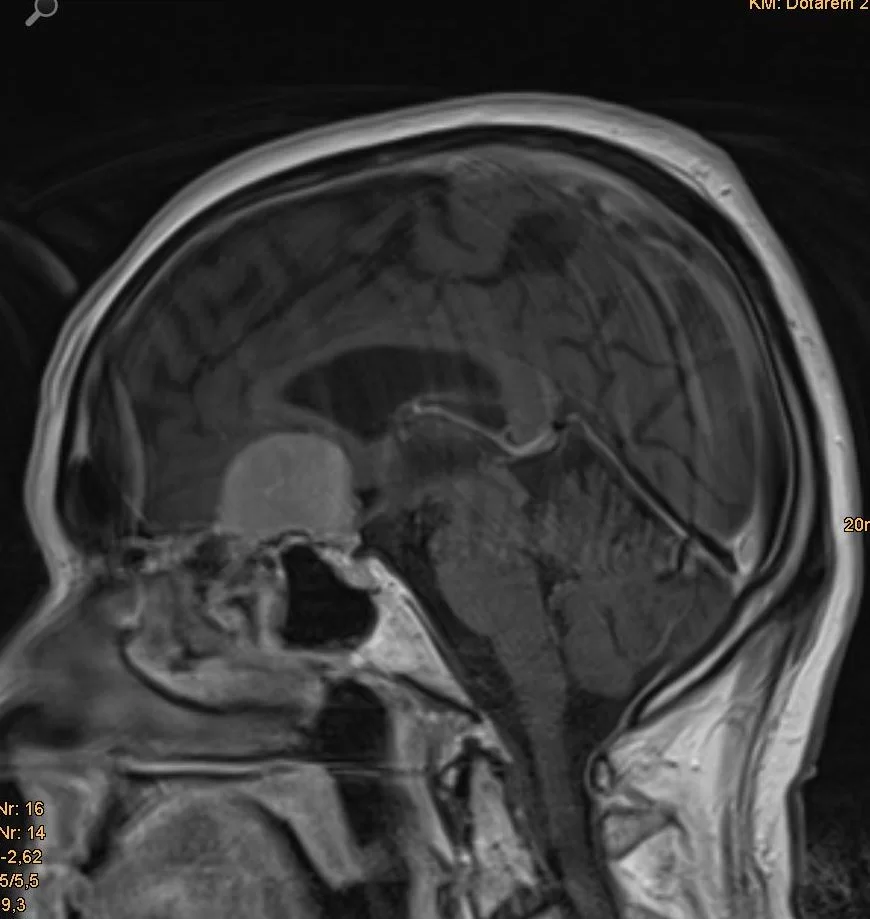

Ευμεγεθες Μηνιγγίωμα Πτέρυγας Σφηνοειδούς οστού

Ασθενής 69ετών με συμπτώματα βραδυψυχισμού και έκπτωση γνωσιακών λειτουργιών. Ο απεικονιστικός έλεγχος με μαγνητική τομογραφία ανέδειξε ευμεγέθη εξεργασία δεξιά, συμβατή με μηνιγγίωμα πτέρυγας σφηνοειδούς οστού.

Περισσότερα